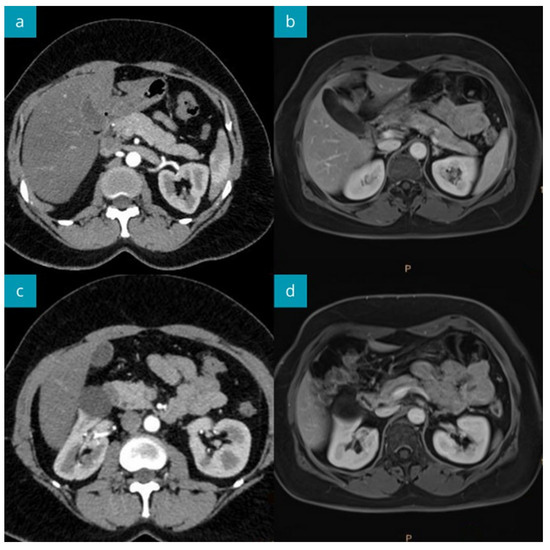

Repeated MRI after 15 months revealed a normal pancreas image (Figure 3). The increased, but lower than previously, CA 19-9 value (1144 U/mL) was still observed in the asymptomatic patient.

Figure 3.

The abdominal CT imaging during the primary diagnostic work-up (a,c), and MRI after 15 months of follow-up (b,d). The head (mildly enlarged), body, and tail of the pancreas show normal structure. Normal pancreas image in MRI performed 15 months later.